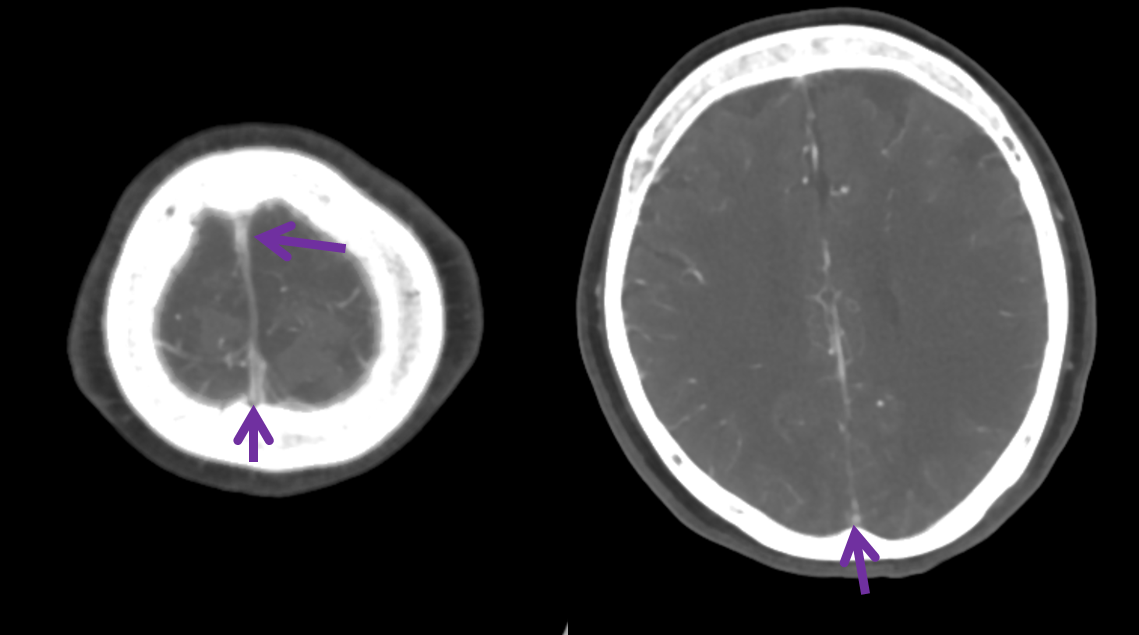

Below is a case of severe venous sinus thrombosis and secondary parenchymal venous infarcts

The explanation for the above tragic pattern is below. On the right, sigmoid and transverse sinuses are patent. However, the Labbe is hypoplastic, and majority of outflow used to go to the Trolard, into the now occluded SSS. There is no other effective way to go — the trolard tries to decompress via a left diploic vein, and convexity tries to access the deep venous system (which normally should not be well-seen in setting of hypoplastic right A1 segment). The left situation is much better, as well-developed superficial sylvian veins drain into the patent Cavernous Sinus. Thus, despite thrombosis of the left transverse and sigmoid sinuses, the left hemisphere is doing better, while the right one, which has patent transverse and sigmoid sinuses, is devastated.

Post venous thrombectomy — with limited results. Note presence of same left diploic vein as seen in right ICA injection, and connection between the distal superior sagittal sinus and the deep venous system via the inferior sagittal sinus.

Sagittal Sinus Thrombosis — collaterals.

All of the above anatomic knowledge can become very useful in evaluation of venous thrombosis. Numerous collateral pathways develop in this setting attempting to compensate for the loss. The most dramatic cases usually involve the largest channel — the superior sagittal sinus. In this case, a man presented with what initially was thought to be vasculitis-related brain hemorrhage. Subsequent workup led to an angiogram, where sagittal sinus thrombosis with extensive trans-cerebral and trans-osseous emissary vein collateral channels was seen. In retrospect, these findings were present on the patient’s earlier contrast MRI. “Venovibe” or other contrast-enhanced MR venograms can very sensitive, particularly when interpreted with the appropriate index of suspicion. Noncontrast 2-D time of flight MRV I consider to be next to useless as a problem-solving technique. Any thin-slice postcontrast T1 study is vastly superior.